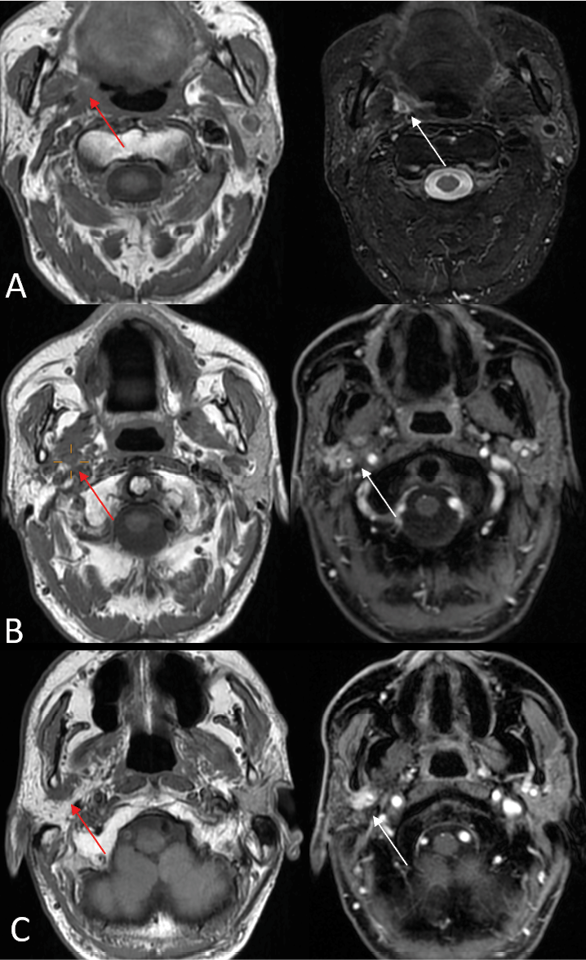

1) PNS commonly presents as enhancement of the affected nerve, which is attributed to the disruption of the blood-nerve barrier caused by the tumor growth and the associated nerve damage [28]. This enhancement is frequently accompanied by nerve enlargement due to multiple pathophysiological processes including tumor infiltration, inflammation, interstitial edema, and neurotrophic factor-induced hypertrophy [1]. However, in some instances, enhancement may occur without appreciable nerve enlargement, thus creating diagnostic challenges in radiological detection. Magnetic Resonance Imaging (MRI) optimally demonstrates both neural enhancement and enlargement, particularly when extending through neural foramina. Pathologic enhancement is characterized by diffuse, uninterrupted enhancement with no clear demarcation from the Perineural Vascular Plexus (PNVP) (Fig. 1, A, B and C) [2]. Careful evaluation of the enhancement intensity, thickness, and symmetry between the sides is essential to identify pathological changes. On CT, although individual nerves may not be well-defined, excessive contrast enhancement in neural foramina or canals can indicate nerve involvement [29].

On MRI, denervated muscles undergo a characteristic pattern of change:

In the acute phase (<1 month), MRI findings are characterized by T2 hyperintense edema-like signals, best visualized on fat-suppressed T2-weighted sequences (Fig. 1 D), and contrast enhancement of the affected muscles, which is most prominent on post-contrast, fat-suppressed T1-weighted images. An increased muscle volume is also noted [29]. During the first four weeks of denervation, there is a shift in water distribution, with a relative decrease in intracellular water and a corresponding increase in extracellular water, while the total tissue water remains unchanged. This redistribution leads to hyperintense signals on T2-weighted MR images, mimicking edema, as the T2 relaxation time of extracellular water is longer than that of intracellular water [31]. Additionally, enhanced contrast uptake is observed in the affected muscles due to increased perfusion and contrast medium accumulation in the extracellular space [31]. Notably, the denervated muscle retains its internal striation, distinguishing it from the muscle infiltrated by tumors, which disrupts the muscular architecture [2]. On PET imaging, there is typically increased 18F-FDG uptake in the affected musculature due to hypermetabolism associated with acute denervation [32].

In the subacute phase (up to 12–20 months), there is a progression from edema-like changes to fatty transformation and chronic modifications in the muscles. While muscles may still exhibit T2 prolongation and contrast enhancement, there is neither an increase nor a loss in the muscle volume. Additionally, T1 hyperintensity becomes apparent, reflecting fat infiltration [33]. In the subacute phase of denervation, PET imaging typically shows normalized or slightly increased 18F-FDG uptake in the affected musculature [32].

The chronic phase of denervation (12–20 months post-onset) is characterized by diffuse fatty infiltration of muscles, which appears as hyperintensity on both T1- and T2-weighted MRI images, along with a reduction in the muscle volume, detectable on both MRI and computed tomography (CT) [33] . Denervation atrophy is most clearly visualized on T1- and T2-weighted images without fat suppression, as the use of fat suppression techniques can obscure the appearance of fatty muscle replacement [29]. In contrast, direct neoplastic muscle infiltration typically results in an increased muscle volume and more heterogeneous signal alterations, with a lower signal intensity compared to the hyperintense changes seen in chronic denervation atrophy [2]. In addition, in this phase on PET imaging, there is muscle atrophy with a decreased 18F-FDG uptake in the affected muscles, along with an increased compensatory uptake in contralateral unaffected muscles, such as the contralateral tongue in CN XII or vocal in CN X cord denervation [1].